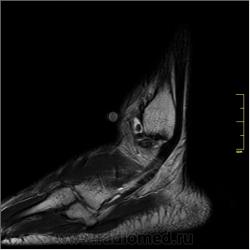

2. По "боковой рентгенограмме" при анализе передних отделов - отметил - бы окостенение мягкотканных компонентов - зеленые стрелки, высказал - бы "недоверие" передне-нижнему контуру дистального эпифиза б/берцовой кости. Возможно отметил, а возможно и нет некоторый субхондральный склероз по заднему коннтуру ладьевидной кости - красные стрелки.

3. Анализируя "задний отдел", конечно отметил-бы наличие ос. тригонум, хротя, это не факт, что, это именно она, а именно дополнительная сверхкомплектная кость - ос тригонум.

4. Возможно, придрался-бы к структуре костной ткани задних отделов таранной кости.

Я считаю, что присутствуют добавочные кости голеностопного сустава: os trigonum, os talus secundarius, os subfibulare, окруженные выпотом, вероятно, реактивного характера в результате избыточной нагрузки.

Валентин Львович! Аналогично - эффект суммации, так прошел срез. Есть выпот, который "наложился" на кость. Это хорошо видно при просмотре полной серии. К сожалению, на сайте поместить полное исследование затруднительно, я поместил только наиболее важные (по моему мнению) срезы.

Все-таки я считаю, что причина болезни до конца не установлена. Некоторые вопросы остались без ответа. С эпифизом б/б кости не все ясно.